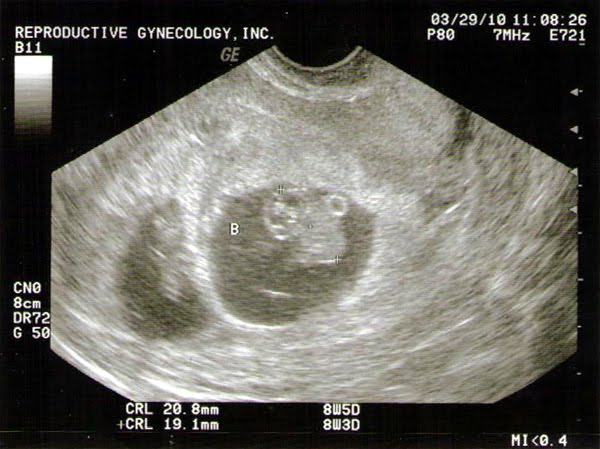

Baby B--you can really make him/her out. See the head, back, and little rump! The little circle by his/her back is the yolk sack. If you look at two weeks ago the yolk sacs were twice the size of them.

Baby CYesterday was our second ultrasound. It was so very cool. They are starting to look like little babies. Additionally, we heard all three of their heartbeats. I thought I would cry, but I think I was so relieved all three were growing and doing well, that I just absorbed what I was hearing. We recorded Baby B's heartbeat. I've tried to get it to upload, but so far no sucess.

I'm still having minor morning sickness. It comes in waves. Friday was the worst it has been. I was sick on and off all day. Crackers and sprite were a beautiful thing. I've gained 4lbs, but I think since I lost 7lbs or so, that really that isn't too bad. Today we are 8w5d. Yesterday each of the babies were measuring 19-20mm. That's an inch!

Week 8 Babies: will be about 8-11 mm CR by the end of the week (uhm..we have super babies. They were 19-20 mm). The baby's hind brain is clearly visible. This week the baby's gonads will become either testes or ovaries. And spontaneous movement begins! Elbows appear and the process of ossification (hardening of the bones) begins. Toe rays become present, almost ready for you to count!